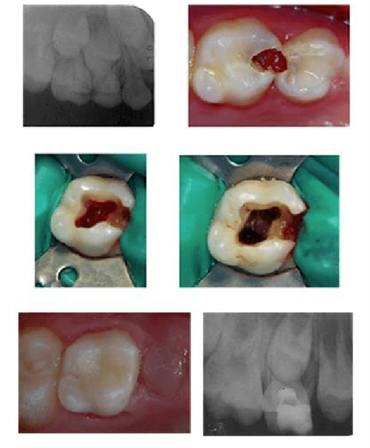

When a tooth is showing signs that a pulpotomy is needed, an x-ray is taken and the tooth is evaluated to determine if the tooth can be treated or if it needs to be extracted.

The area is then numbed. If decay is present in the tooth, the decay is removed. After the decay has been removed, the pulp of the tooth is then removed. Only the top section of the pulp is removed, not the pulp within the roots of the tooth.

After the pulp has been removed, a cotton pellet damp with formocresol is placed in the tooth. The formocresol will sterilize the inside of the tooth as well as “mummify” the remaining pulp. Formocresol is the most common method used, but some dentists may choose to use a laser, Ferric Oxide, electro surgery, or MTA.

The cotton pellet remains on the tooth for a few minutes, then it is removed. Once the cotton pellet is removed, the opening is sealed with a Zinc Oxide and Eugenal material. The most common material is IRM, which is a putty-like material that can be molded to the inside of the tooth and will harden after a few minutes.

Once the material has hardened, a permanent or temporary restoration can be placed on the tooth. For many children, a stainless steel crown is used to protect a primary tooth. Stainless steel crowns are often used because they provide enough protection for the tooth until the tooth will naturally loosen and fall out. A stainless steel crown is also less expensive than a more permanent porcelain crown. If the tooth is a permanent tooth, a porcelain crown may be recommended.